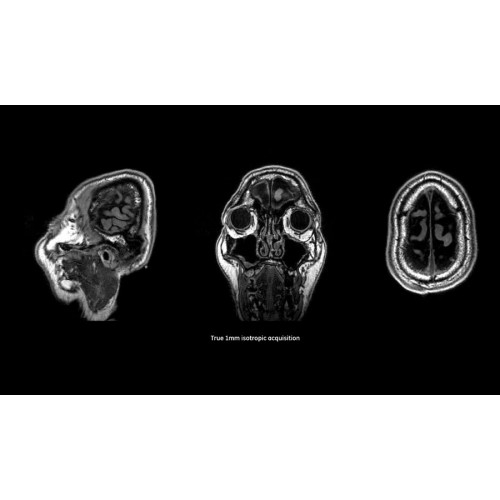

МРТ аппарат GE SIGNA Pioneer 3.0T

Детализация изображений

Система SIGNA Pioneer воплощает поразительные достижения в области визуализации. Передовая технология Total Digital Imaging (TDI) позволяет добиться большей четкости изображений и на четверть повысить соотношение сигнал/шум.

• Технология Direct Digital Interface (DDI) использует независимый аналого-цифровой преобразователь для оцифровки сигнала от каждого из 97 радиочастотных каналов, что обеспечивает значительное увеличение качества за счет уменьшения фонового шума.

• Технология Digital Micro Switching (DMS) — это следующее поколение технологий радиочастотных катушек, основанное на замене аналоговых схем блокировки сверхбыстрыми микропереключателями (MEMS), что делает возможным быстрое переключение катушек для дальнейшего расширения возможностей визуализации с нулевым TE.

• Технология Digital Surround Technology (DST) — это новая технология объемной оцифровки данных, объединяющая сигналы от каждого элемента катушки. Прекрасное соотношение сигнал/шум и чувствительность поверхностных катушек в сочетании с превосходной однородностью и высокой проникающей способностью встроенной радиочастотной катушки — все это позволяет создавать качественные изображения не только позвоночника, но и всего тела.

Помимо технологии 97 РЧ-каналов, SIGNA Pioneer использует магнит 3.0Т высокой однородности, предназначенный для повышения качества визуализации во всех областях, а также закладывающий прочный фундамент для долгосрочных инвестиций и роста клинических возможностей.